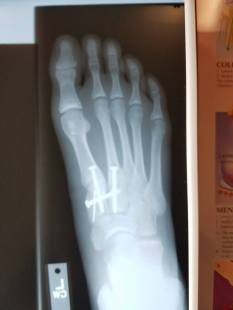

post-op-x-ray

Post-op x-ray showing the three screws that were used align all of the bones so that her ligament can heal properly.